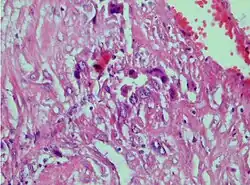

| Photomicrograph showing proliferating intermediate trophoblast with scarce cytotophoblastic and syncytiotrophoblastic elements | |